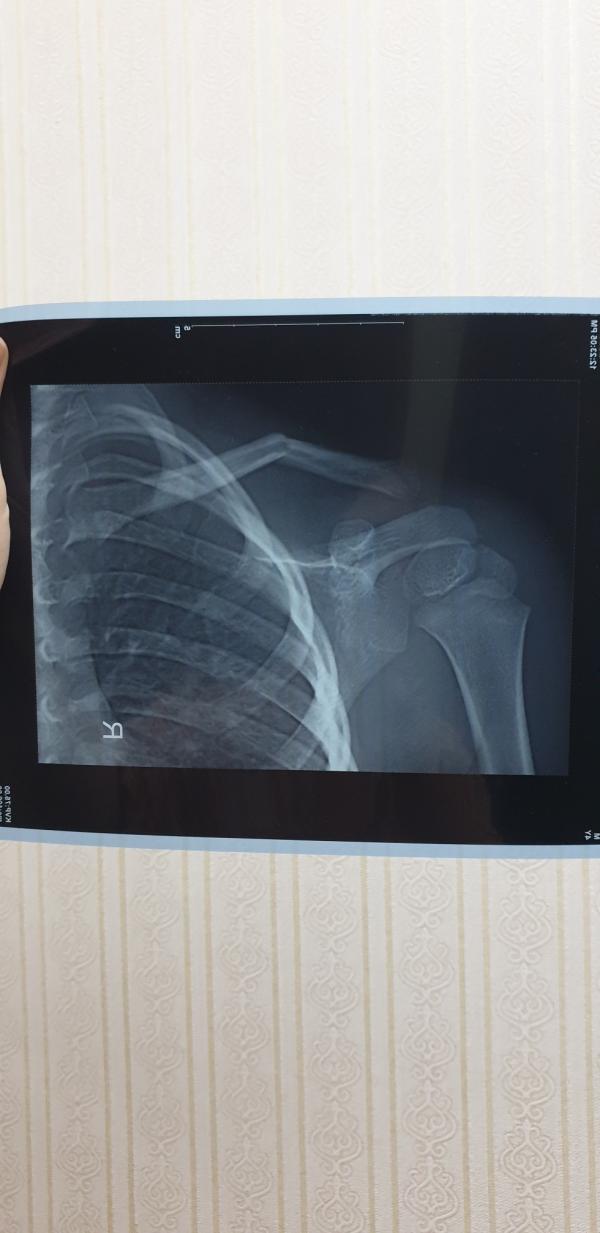

@anik3991, брату кольца поставили,операцию нужно сделать сказали(

Лежал на кровати замотавшись в плед и упал, видимо прям на плечо , Я думала он плачет от удара головой, так как там шишка сразу вышла, а оказалось ключица 😑

Мой брат сломал ключицу,давно ещё,лет 10 назад,она у него неправильно срослась(друг на дружке эта сломанная кость(как на снимке)